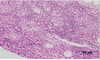

Adrenocortical carcinoma

In dogs, adrenocortical tumors mostly arise from the

In dogs, adrenocortical tumors mostly arise from the zona fasciculata

Many adrenocortical neoplasms are

Many adrenocortical neoplasms are non productive (exact proportion not reported).

Roughly 50% benign/malig; Around 10% bilateral.